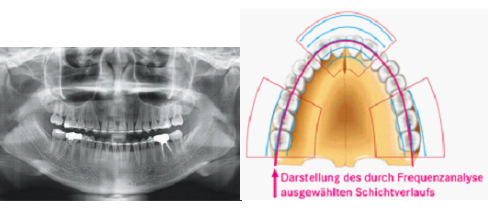

Digitales Panoramaaufnahmegerät zur Darstellung des gesamten Kieferbereiches sowie ausgewählter Aufnahmebereiche (Kiefergelenke, Kieferhöhlen,…

Das PaX-Primo ist ein echter Technologiesprung in der digitalen Panorama-Röntgen-Technolgie. Statt einem Line-Sensor, wie herkömmliche OPGs, verfügt das Primo über einen Area-Sensor. Der Area-Sensor nimmt während eines Umlaufs 13 Schichtlagen auf. Die schärfsten Bereiche jeder Schichtlage werden mit dem ALSA [Automatic Layer Selection Algorithm] zu einem Bild zusammengefügt.

Die ALSA-Technologie bringt neben der verbesserten Bildqualität noch weitere Vorteile mit: die Patientenpositionierung wird wesentlich vereinfacht. Lediglich mit 2 Laser-Licht-Visieren wird der Patient einfach und schnell positioniert. Der Area-Sensor, der in 13 Schichtlagen aufnimmt kann Positionierungsfehler und Bewegungsartefakte weitestgehend ausgleichen.